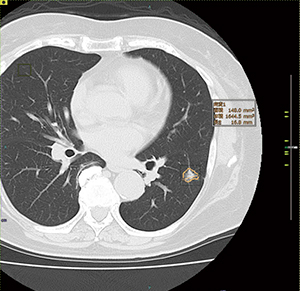

AI技術を活用し胸部CT画像による肺がん診断

SAI viewerでは,画像解析オプションとしてAI技術を活用した機能を搭載している。その一つとしてV1.3で追加されたのが,肺結節検出機能と肺結節性状分析機能だ。肺結節検出機能では,胸部CT画像から肺結節の候補を自動で検出して検出箇所をマーキングして表示し,肺結節の見落とし防止を支援する。肺結節性状分析機能は,結節の性状分析,所見文候補の自動生成などを行いレポート作成を支援する。

同院では,肺結節検出機能を使わずに読影後,SAI viewerがピックアップしたものを再びチェックするフローで運用している。鈴木先任准教授は,「肺結節の読影では,肺の血管径と同程度の大きさの時に見逃しやすいことがありますが,SAI viewerの検出機能を使うことで結節の候補がピックアップされます。それを再確認して答え合わせをする感じですが,数か月の使用経験で検出機能がなかったら見逃していたというケースも実際に経験しています」と話す。運用について菊地医師は,「SAI viewerの検出機能は,まず自分で読影したかどうかのアラートが出て承認しないと使えません。画面では,SAI viewerがピックアップした候補と自分でチェックした結節が,スライス位置でタグとして対比して表示されて,自分がチェックしなかった結節が一目で確認できるので使いやすいですね」と説明する。

SAI viewerの検出結果について鈴木先任准教授は,「まだ検証したわけではありませんが,結節は少し過剰にピックアップされている印象です。その方が後から確認して除外できるので安心です」と言う。京極教授は,「オーバーリーディングだなと感じますが,トータルで見ると優秀だと思います」と述べる。肺結節性状分析機能では,読影医が指定した結節のサイズ計測,辺縁部,内部構造などの性状分析を行う。さらに,比較読影に必要な病変の推移を並べて経時的な観察を1画面で可能とする“フォローアップビュー”も搭載されている。

肺結節検出機能

コンピュータ支援診断(CAD)で肺結節の候補を検出する。検出されたスライスにはスライダーバーにマークが表示され,医師がフォロー対象として指定した候補には計測結果を提示する。